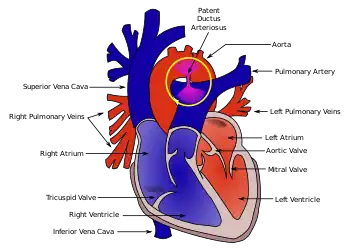

| Diagram of a cross-section through a heart with PDA | |

Patent ductus arteriosus (PDA) is when the connection between the aorta and pulmonary artery (the ductus arteriosus) fails to close after birth.[3] Early on there are generally no symptoms; however, later shortness of breath, failure to gain weight at a normal rate, or difficulty exercising may occur.[1][4] Complications may include heart failure, pulmonary hypertension, necrotizing enterocolitis, kidney failure, and intraventricular hemorrhage.[2]

Illustration of Patent Ductus Arteriosus

Illustration of Patent Ductus Arteriosus Patent ductus arteriosus